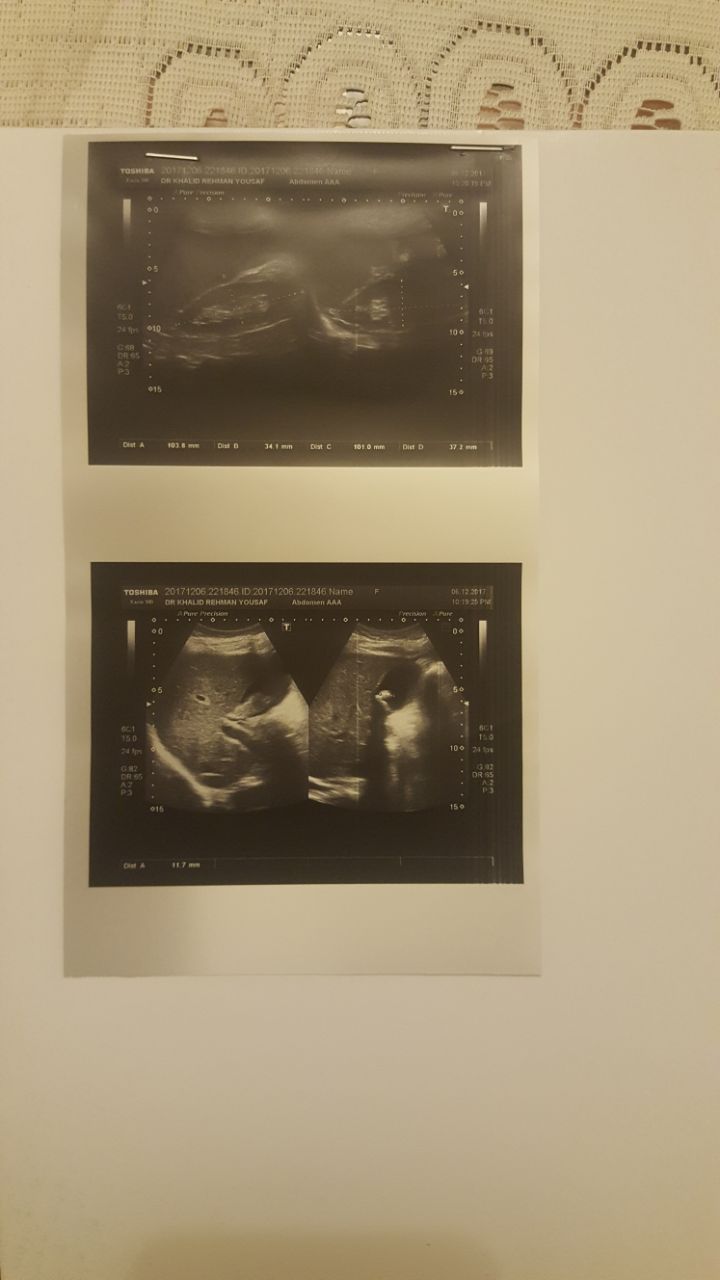

Asking for Sister, Female, 27 years old, lahore

Should it be treated surgically or with medicine.

Thanks for asking. I think we should know first about the history of the patient and it should include detailed examination. As ultrasound has already been done and fluid is also aspirated from the abdomen. We should wait for the reports of aspiration. I think if reports are not conclusive then we have to go for the CT ABDOMEN AND PELVIS WITH CONTRAST. I wish there would be ESR in the blood test which is missing in CBC. CA 125 is also required.....

There is an acoustic shadow in the gall bladder (pitta) which can either be stones or grit . depending upon what are your complaints you need to get an examination and discuss in details what are you suffering from for an appropriate plan of treatment